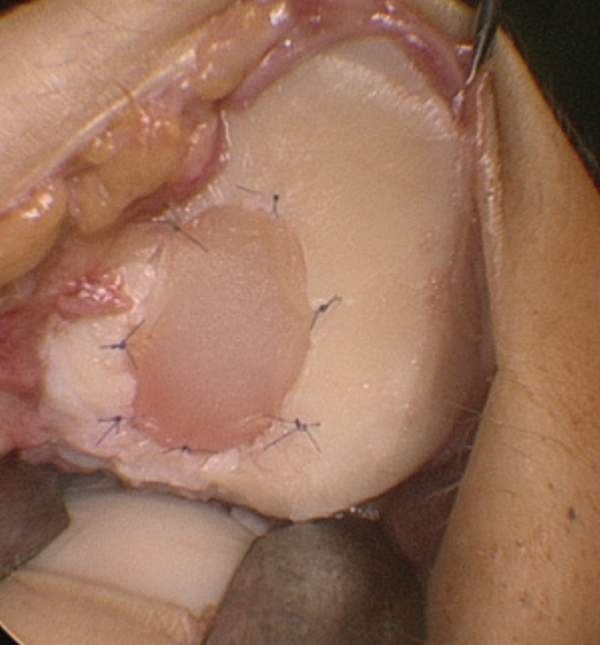

Knorpeltransplantation

(Matrixgestützte autologe Chondrozytentransplantation, MACT)

Das biologisch hochwertigste Verfahren. In einem ersten Eingriff werden körpereigene Knorpelzellen entnommen und im Labor in einer Membran angezüchtet. Diese wird bei einem zweiten Eingriff in den Knorpeldefekt eingebracht (siehe Abb. 1). Kooperationspartner des RKU ist für dieses Verfahren die Firma Tetec in Tuttlingen. Dieses Verfahren kommt für Knorpelschäden ab einer Größe von 2,5 cm² in Betracht.